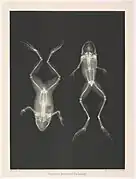

Caméléon Grenouille

Grenouille poissons